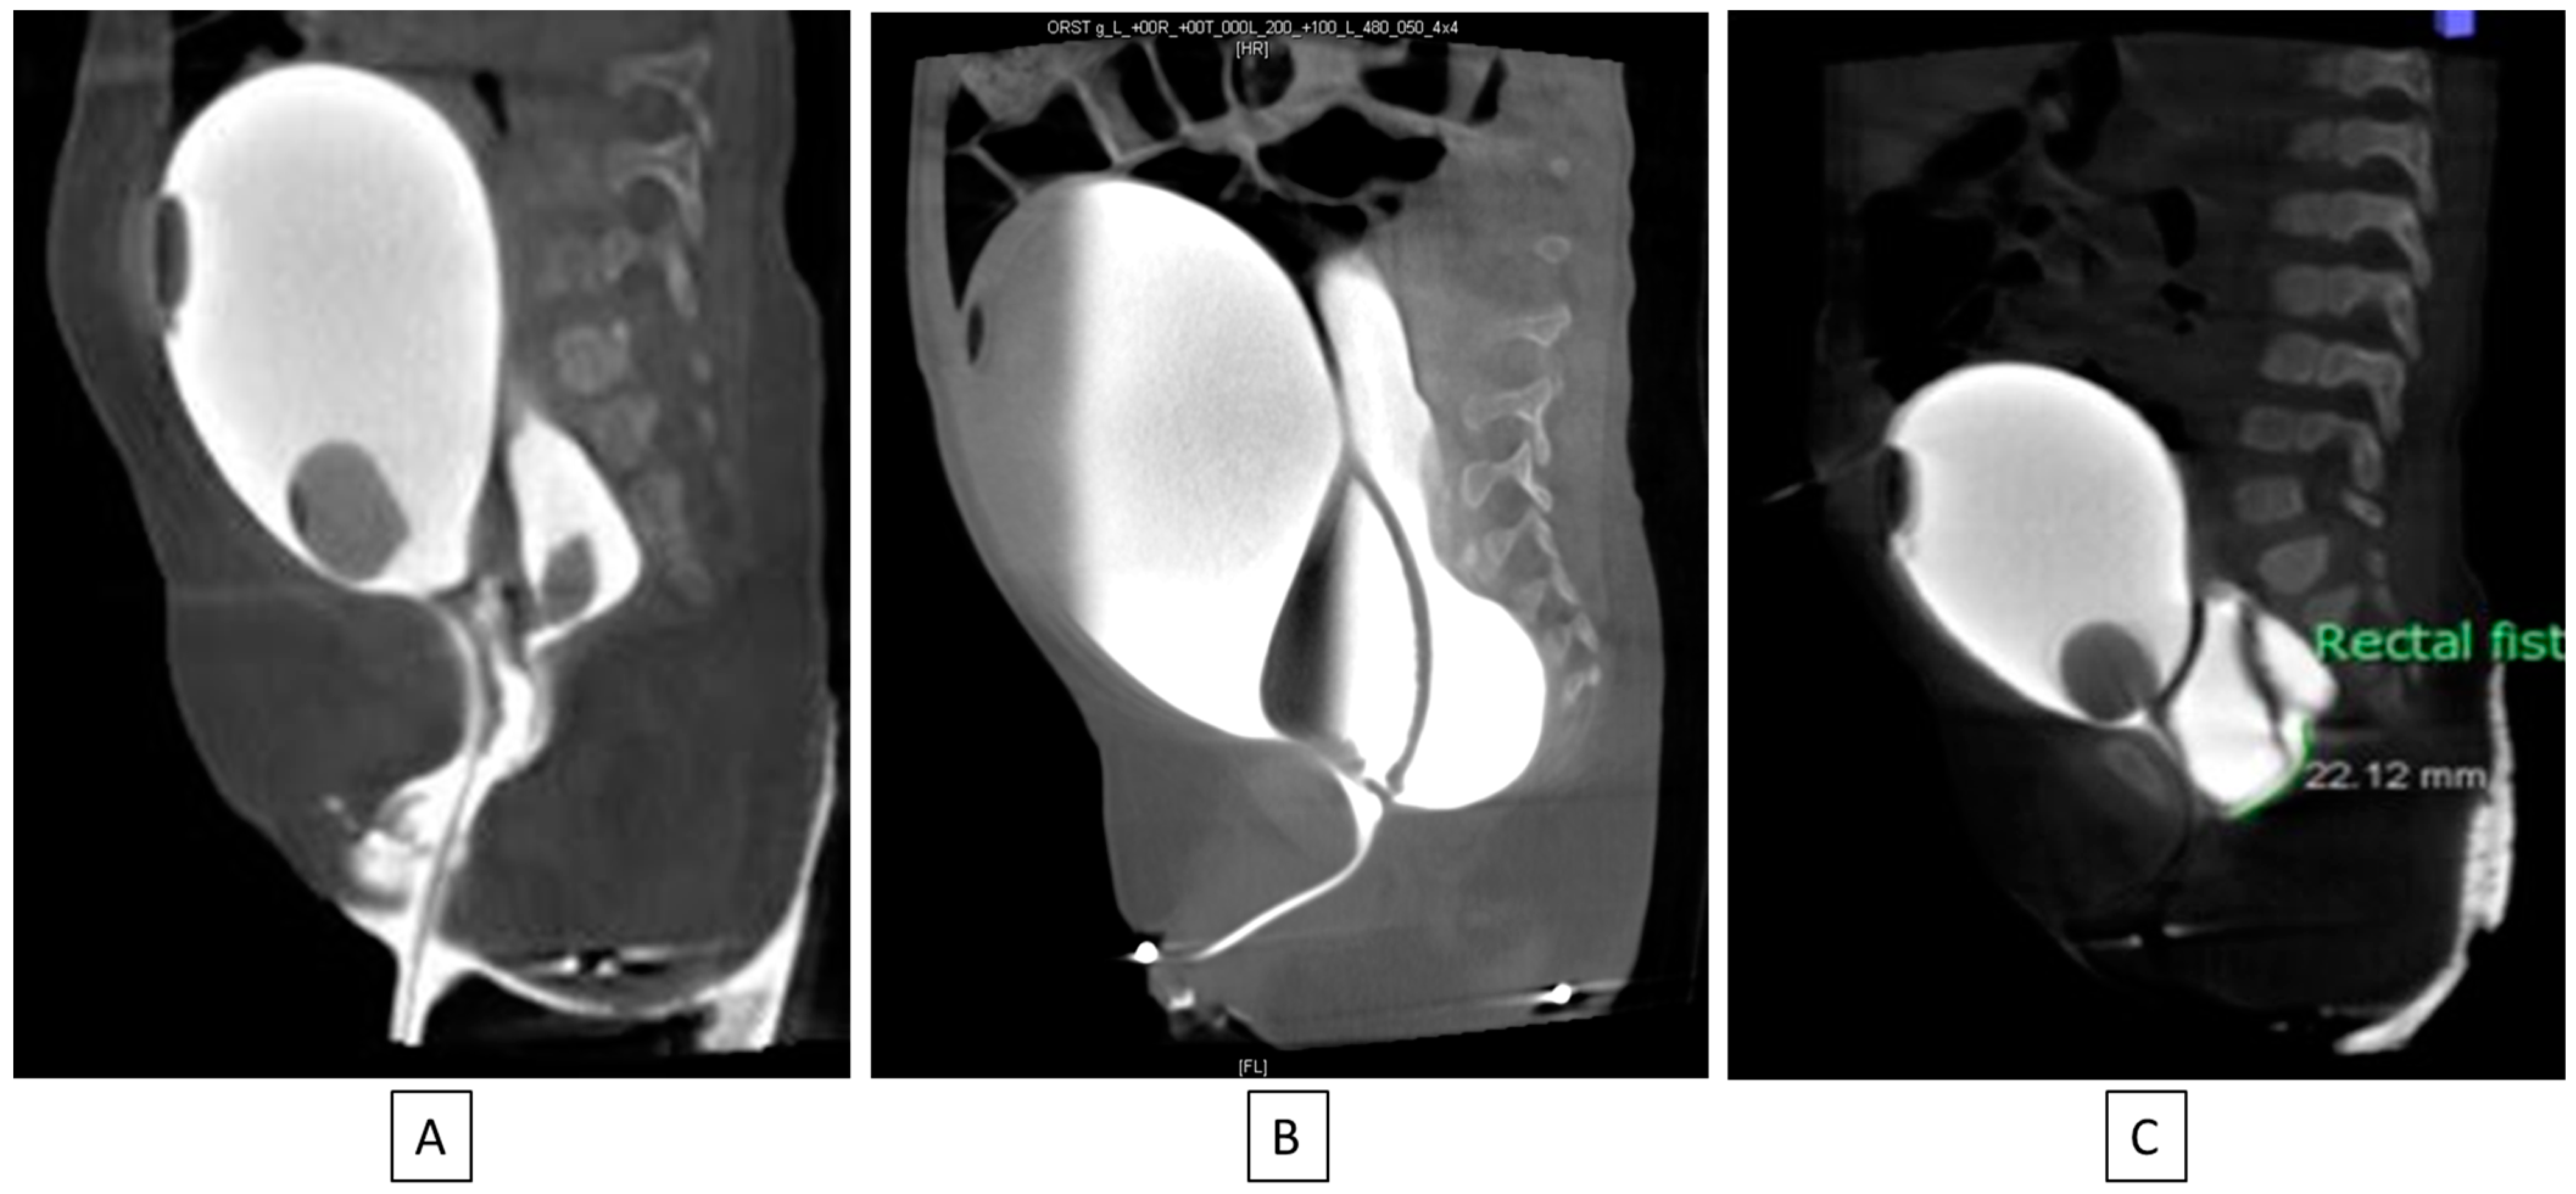

6.9. Cloaca Management

The original cloacal repairs described by Hendren all involved separating the vagina from the urinary tract and reconstructing a neourethra. With the major advance of total urogenital mobilization (TUM), the vagina and urinary tract could be brought down as a unit. Thanks to collaborative teamwork between colorectal and urologic surgery, it became clear that the TUM procedure was only appropriate for a patient with a short common channel (<3 cm) and a long urethra (>1.5 cm). Understanding this distinction is critical to recreating the best possible anatomy for the child and minimizing unexpected changes to surgical plans intraoperatively. For example, if a TUM is performed for a patient with a short urethra (less than 1.5 cm), this would lead to an anatomic situation whereby the bladder neck is left too close to the perineum and below the urogenital diaphragm, leading to urinary leakage. On the other hand, if a TUM is performed in the case of a cloaca with a high confluence (long common channel) and the surgeon finds that the UG sinus does not reach the perineum, then a urogenital separation would be required. Since the anterior urethra would already have been dissected during the TUM, this maneuver can lead to urethral loss. Therefore, it is vital to know in advance the common channel and urethral lengths, which has been made possible by precision cystoscopy and cloacogram imaging [42,43] [Figure 5].

Figure 5. If urethral length is greater than 1.5 cm (A,B), a total urogenital mobilization can be performed; if it is less than 1.5 cm (C), the cloacal repair will need a urogenital separation [40].